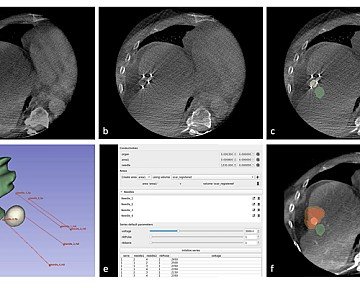

Parmi ses innovations notables figure l’aiguille courbe brevetée mondialement, permettant d’atteindre des zones jusque-là inaccessibles. Une invention honorée par l’Académie Nationale de Médecine.Le Dr Brunner a également développé des techniques innovantes pour le traitement des pathologies du dos et des tumeurs, notamment par cryothérapie.Son engagement constant dans la recherche et l’innovation a contribué à positionner le CHPG comme une référence internationale en radiologie interventionnelle.